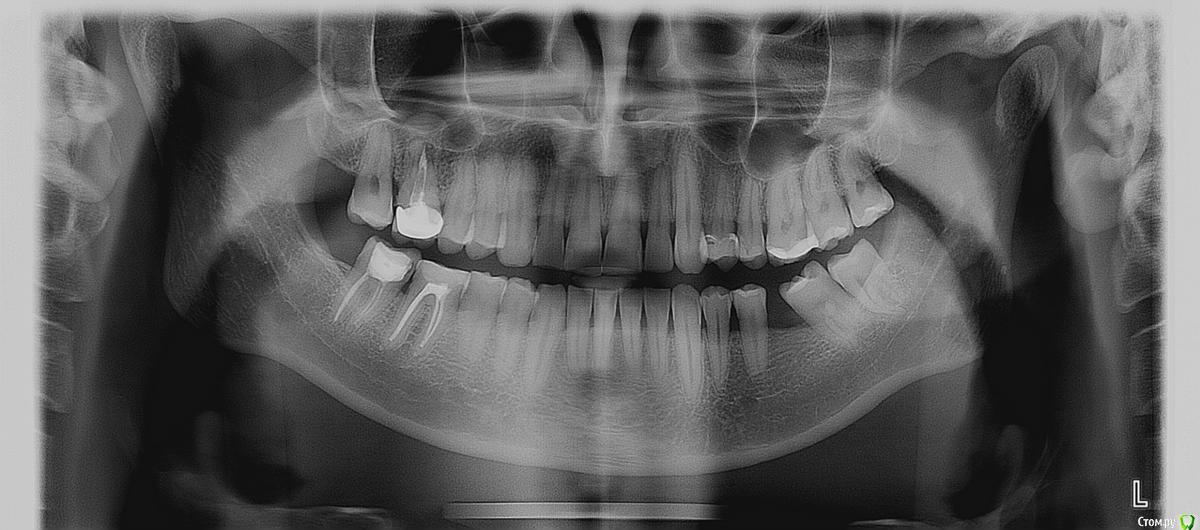

Maktub Опубликовано 10 августа, 2016 Поделиться Опубликовано 10 августа, 2016 Здравствуйте. Нижняя 7 справа. Скол пломбы, при лечении был поставлен диагноз хронический периодонтит. Стоимость лечения с коронкой около 45тыс, имплант примерно также. Еще думал просто удалить и забить.И верхняя 6 с коронкой, справа, под ним киста. Удаление? Ссылка на комментарий

red_butler Опубликовано 10 августа, 2016 Поделиться Опубликовано 10 августа, 2016 Всмысле? Вы про отсутствующий? да, зубы переместились А киста удаляется что ли? кисты нет, есть периодонтит и реакция слизистой оболочки верхнечелюстного синуса. Для начала терапевтическое лечение 1 Ссылка на комментарий

Fibez Опубликовано 11 августа, 2016 Поделиться Опубликовано 11 августа, 2016 Вы выложили ОПГ 1 Ссылка на комментарий